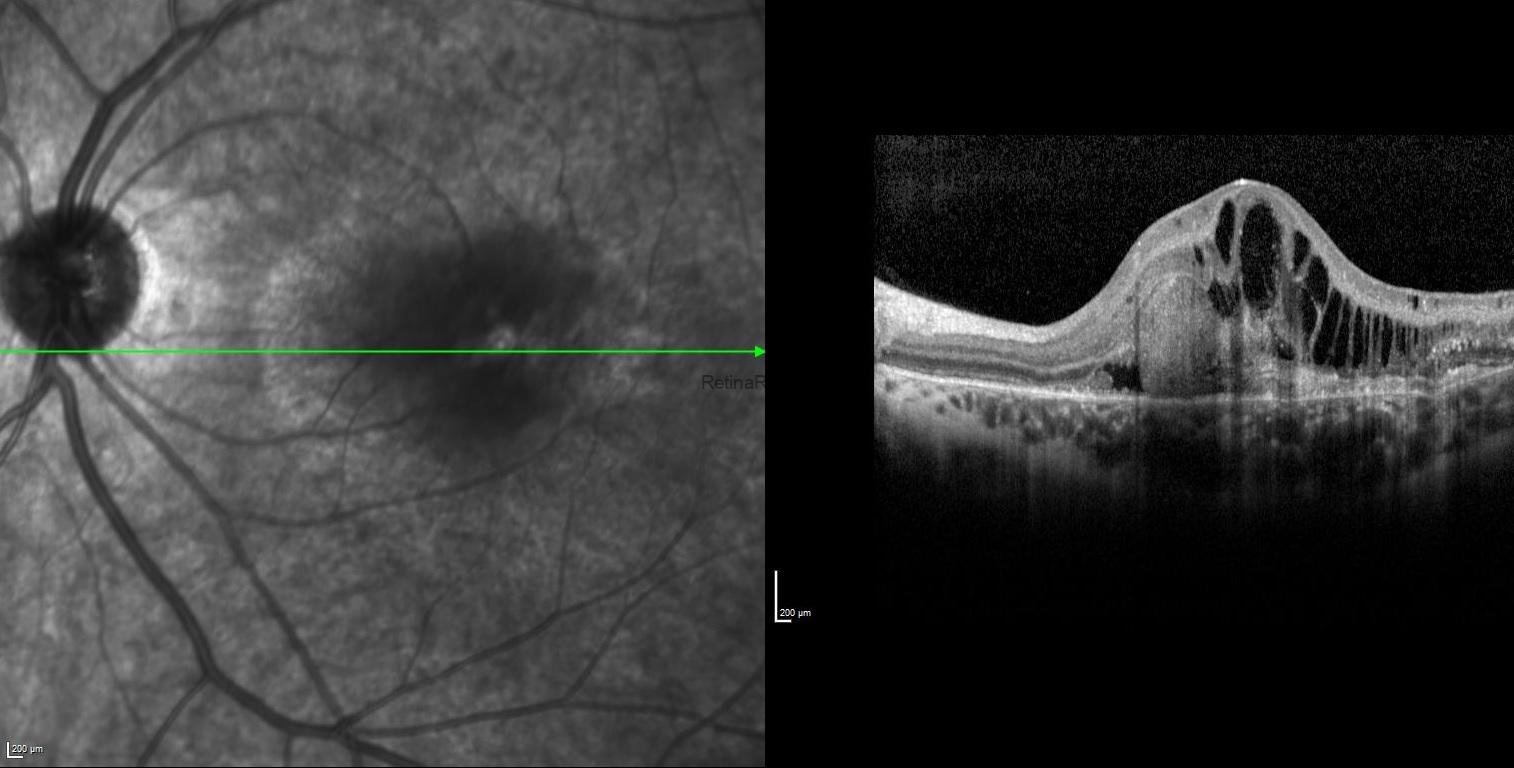

SD-OCT of the right eye showed attenuated inner segment–outer segment junction, absent upward displacement of subfoveal ellipsoid zone band, and mottled retinal pigment epithelium, while it revealed thickened and elevated retinal layers at the macula due to the subretinal and intraretinal fluid with foveal and extrafoveal protruding hyper-reflective material in the left eye.